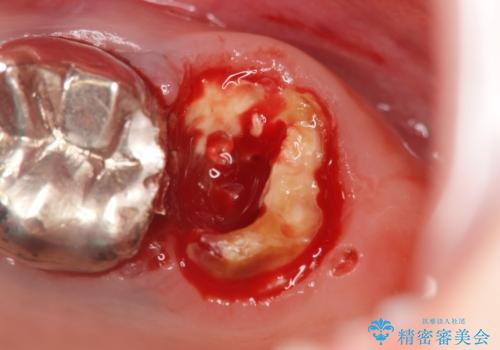

X線検査の結果、左上6には歯根破折、左上7には銀歯の下に大きな虫歯の再発が認められ共に抜歯をせずには症状の改善が見込めない状況です。

奥歯を2本失ったのち、しっかりと噛める環境へと整備するため、しっかりと骨の造成を行い清掃性を高めたインプラント治療を行っていくこととしました。